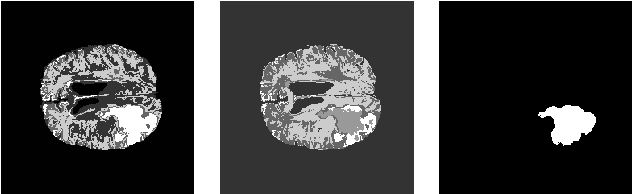

Abstract:Glioma is a common type of brain tumor, and accurate detection of it plays a vital role in the diagnosis and treatment process. Despite advances in medical image analyzing, accurate tumor segmentation in brain magnetic resonance (MR) images remains a challenge due to variations in tumor texture, position, and shape. In this paper, we propose a fast, automated method, with light computational complexity, to find the smallest bounding box around the tumor region. This region-of-interest can be used as a preprocessing step in training networks for subregion tumor segmentation. By adopting the outputs of this algorithm, redundant information is removed; hence the network can focus on learning notable features related to subregions' classes. The proposed method has six main stages, in which the brain segmentation is the most vital step. Expectation-maximization (EM) and K-means algorithms are used for brain segmentation. The proposed method is evaluated on the BraTS 2015 dataset, and the average gained DICE score is 0.73, which is an acceptable result for this application.